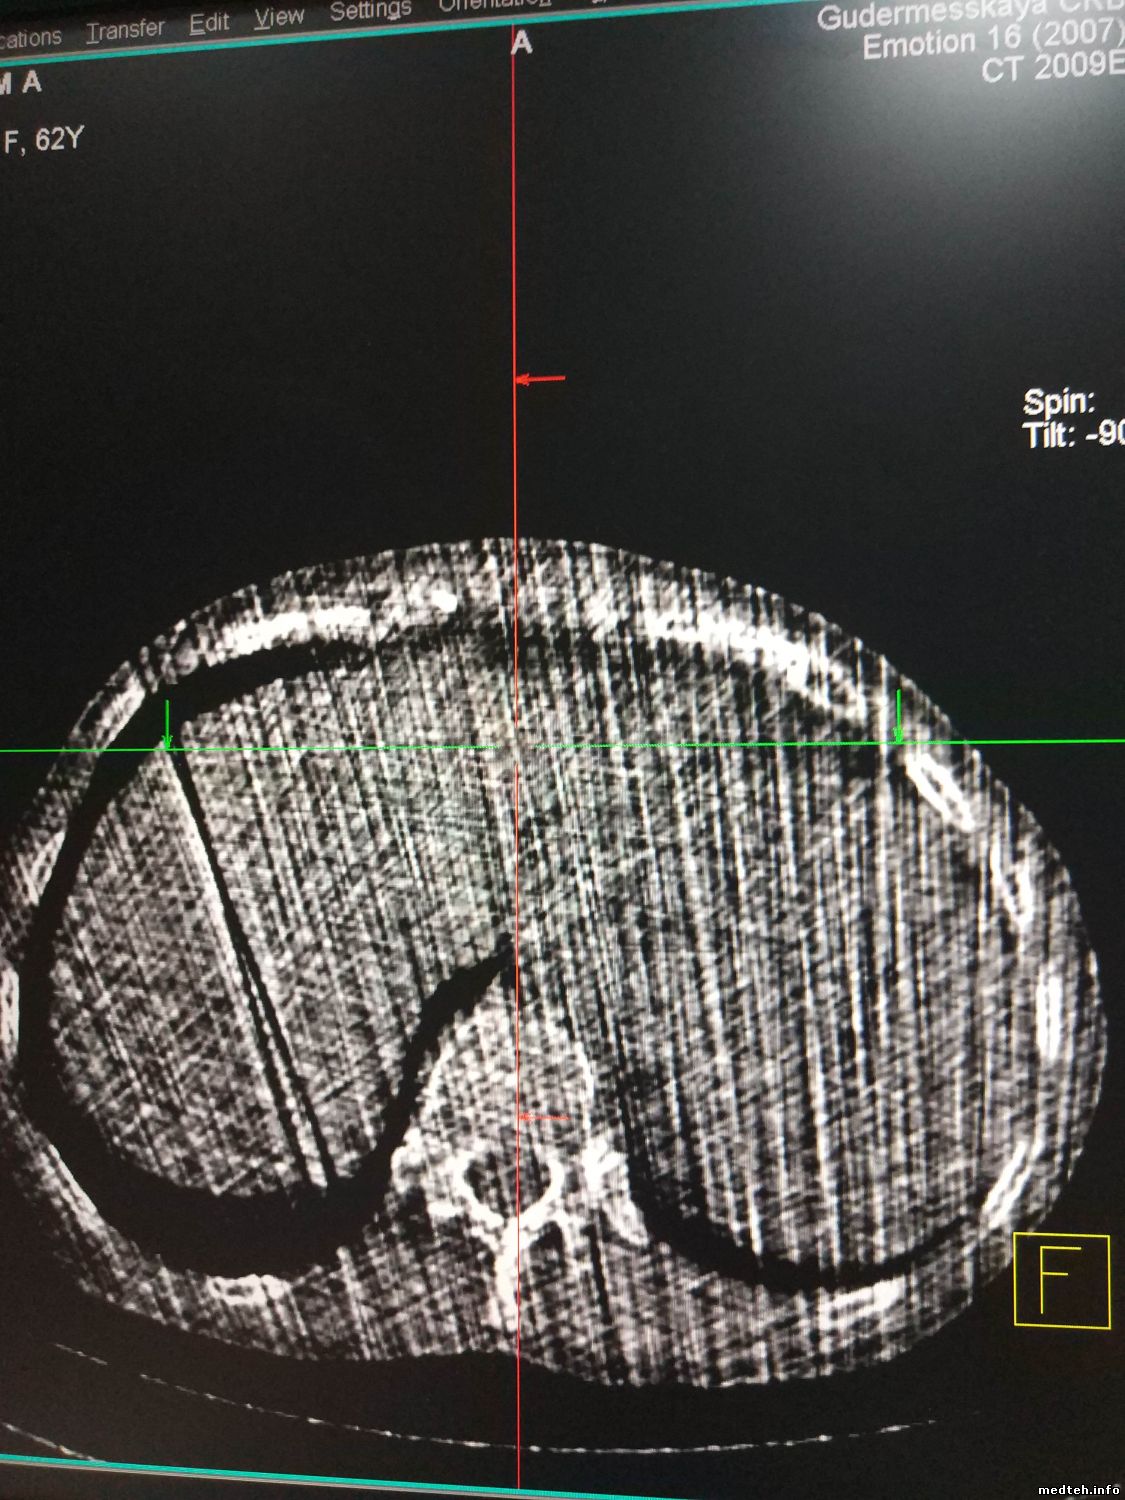

Доброго времени! Столкнулся с артефактом который появляется переодически ошибки при этом не даёт . Кто что думает...?

1982181.jpg (228.6 Kb) · 1606727.jpg (311.5 Kb) · 4363118.jpg (258.9 Kb)

но обязательно первым делом после просмотра лога проверить щётки, и кольцо с энкодером на наличие грязи(было похожее когда на кольцо энкодера прилипла маленькая козявочка, откуда она там взялась х.з. но и ошибки были... причём так же то были артефакты то нет).... если там всё нормально тогда делать тесты и смотреть